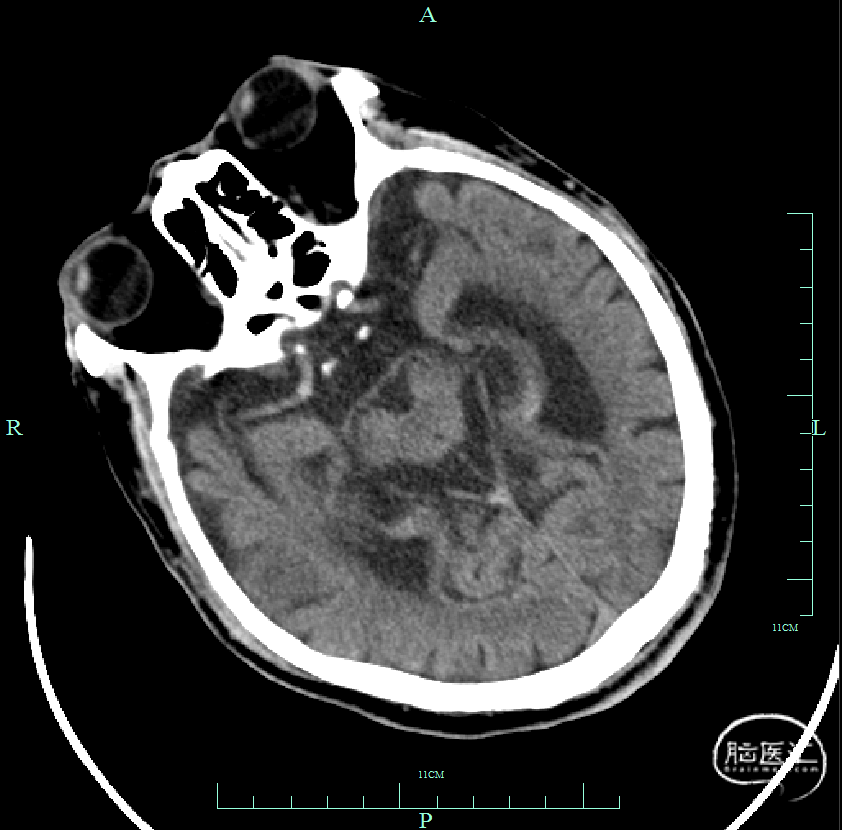

右颈动脉正位

右颈动脉侧位

左颈动脉正位

左椎动脉正位

患者意识障碍,左侧肢体偏瘫,NIHSS评分12分。头颅CT:颅内未见出血。DSA:右侧颈内动脉闭塞。发病时间1.5小时。无明确手术禁忌。